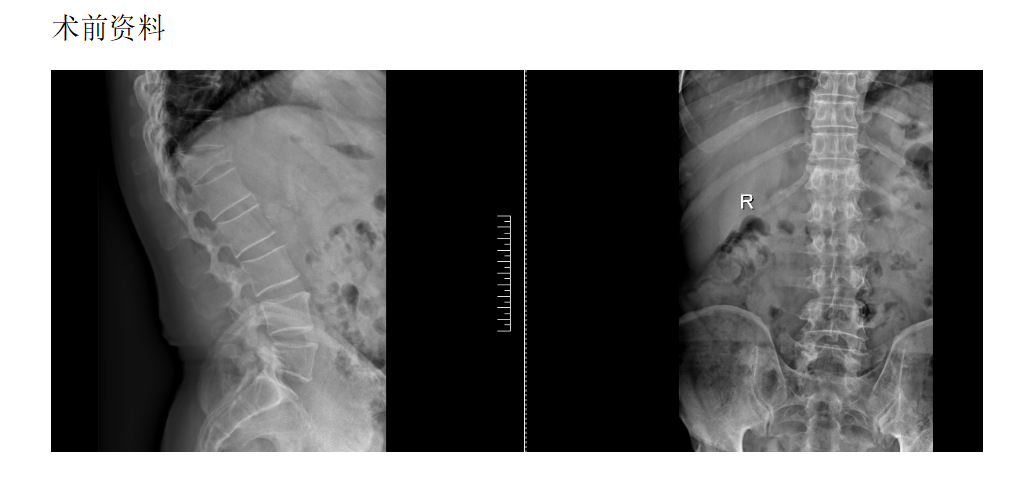

脊柱外科组(骨折、畸形、复杂融合固定)

脊柱骨折病历

现病史:半月前坐凳子时不慎摔倒出现腰部疼痛、酸困,无下肢疼痛麻木不适,弯腰活动受限,行走及站立时疼痛加重,平卧休息稍减轻,无发热,无下肢局部红肿,未治疗,上述症状持续加重,为求诊治,现来我院,遂以“T12椎体骨质疏松性压缩骨折”为诊断收住我科。发病以来,饮食正常,睡眠一般,体力正常,大小便正常。